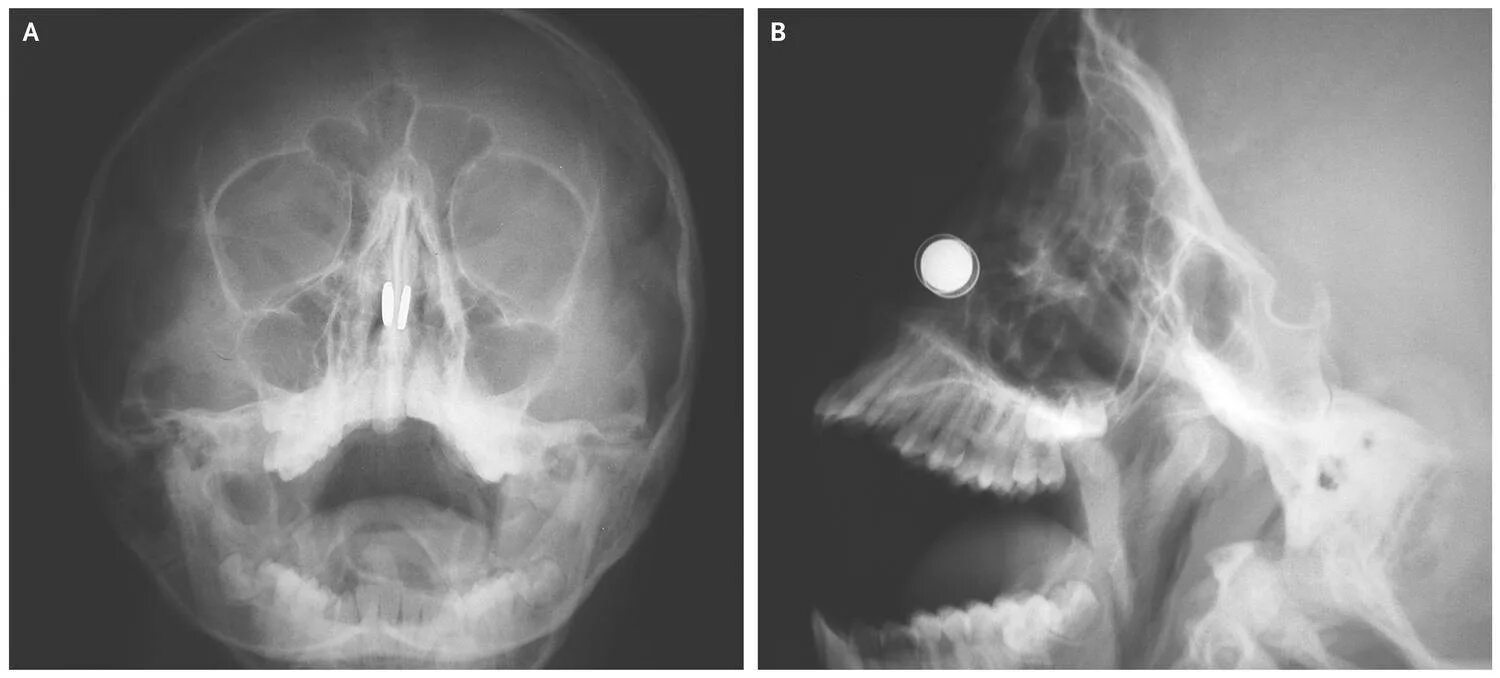

Кленовые носики на носу. носики из клена. клен на нос. кленовые семена на носу.Семечко носКленовые носики на носу. носики из клена. клен на нос. семечка от клена на нос.Инородное тело в носу у ребенка. инородный предмет в носу у ребенка. маленький нос.Семечко носИнородное тело лего в носу. у детей инородное в носу.Носики из клена. вертолетики на носу. носики клена на носу. клен на нос.Анатомия носа хрящи носа. хрящевой скелет наружного носа. сошниково-носовой хрящ анатомия.Семечко носКостная перегородка полости носа анатомия. полость носа анатомия кости.Ринолит полости носа рентген. инородные тела носа рентген. инородный предмет в носу.Инородное тело в носу у ребенка. инородное тело в носу симптомы. инородные тела полости носа. инородный предмет в носу у ребенка.Инородное тело в носу симптомы. инородные тела носа классификация. инородное тело в носу у ребенка. симптомы наличия инородного тела в носу.Семечко носКосточка вишневая в носу. возможно попадание косточки.Ребенок засунул орех в нос. вставляют детям в нос рот.Инородные тела носа первая помощь. попадание инородного тела в нос. инородных тел в ухо глаз нос. инородное тело в носу у ребенка.Семечко носВыпуклый нос.Инородные тела носа рентген. извлечение инородного тела из полости носа. перфорация носовой перегородки.Семечко носИнородное тело полости носа удаляют. удаление инородного тела из носа ребенка.Семечко носГорбоносов игорь ринопластика. кривой нос у мужчин.Нос с горбинкой. убирание горбинки носа. ринопластика кости носа.Болит кость носа на переносице. грушевидное отверстие носа.Первая помощь при попадании инородного тела в нос ребенка. способы удаления инородных тел из полости носа. инородное тело в носу у ребенка. инородный предмет в носу у ребенка.Подсолнечник плод семянка. семя семянка семечка. семечко в разрезе. семянка подсолнечника в разрезе.Семена груши. семена яблока. семечко яблока. семечко от яблока.Семена яблони. семечко от яблока. семя груши. семечки от груши.Семечко носКонопляное семечко ростки. прорастание семян каннабиса. пророщенные семена конопли. пророщенное семя канабиса.Семечко носСемечко носСемечко дерева. семена деревьев. семечко и плод. семя яблока.Анатомия носа костно-хрящевая перегородка носа. назовите анатомические отделы носовой перегородки. носовая перегородка хрящ строение. костная перегородка полости носа анатомия.Семечко носАнатомия носа хрящи носа. наружный нос строение хрящи. кости и хрящи носа анатомия.Семечко носКолумелла носа операция. келоидный рубец ринопластика. искривление колумеллы носа.